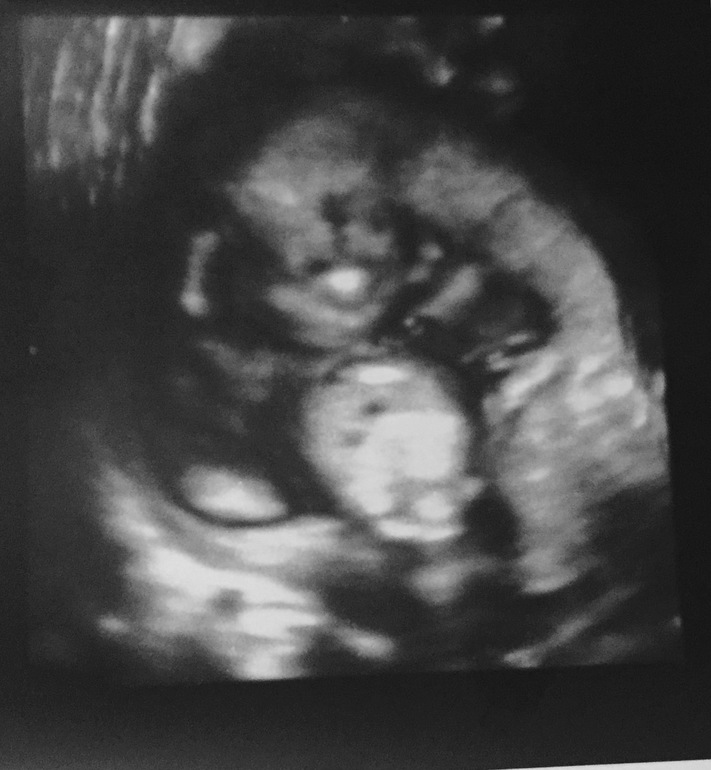

По развитию мы стандартно опережаем на 4-5 дней, всё у нас отлично и растёт МАЛЬЧИК! Это уже 100%.

В 12 недель НС сказала, 90% мальчик, сейчас уже без малейшего сомнения растёт мужичок! Мой сыночек, моё счастье! А вот наше достоинство во всей красе

Папа аж прослезился)) И всё твердит: -Неужели я дождусь в своей жизни сына? Пока не родится, наверное не поверю